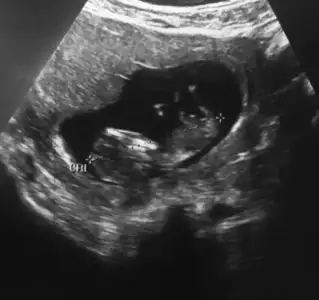

Kız sanki ama emin olamadım net degil cnm olursa başka usg paylaşınSadece bunlar var

Net çekmeye çalıştım ama burdanmı öle acaba anlamadım saglıklı olsun da ama istedigim de kızKız sanki ama emin olamadım net degil cnm olursa başka usg paylaşın![]()